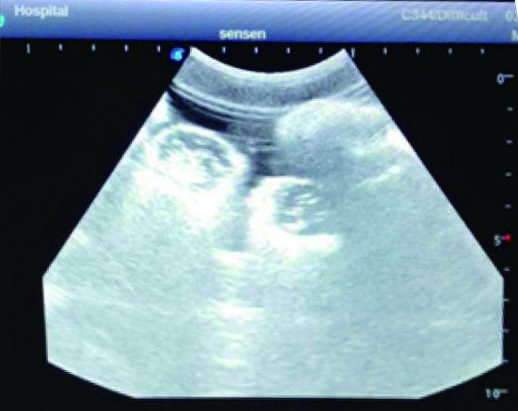

2)  Real clinical ultrasound images with clear anatomical structures like intestines, part of the liver, arteries and veins, etc.